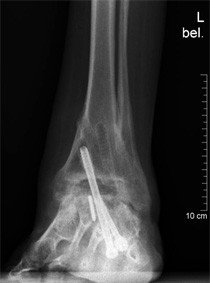

Im Jahr 2006 stellt sich die Patientin in der Fusschirurgie der Schulthess Klinik vor. Die Untersuchung zeigte ein hinkendes Gangbild mit Entlastung des linken Fusses. Der Fuss selbst zeigte eine Fehlstellung als Residuum der angeborenen Klumpfussdeformität. Das Bewegungsausmass im Bereich des oberen Sprunggelenkes betrug 5° nach oben und 10° nach unten. Das gesamte Gelenk stellte sich überwärmt und druckschmerzhaft dar. Die im Rahmen der Konsultation durchgeführten Röntgenaufnahmen zeigten, dass die untere Prothesenkomponente, welche im Bereich des Sprungbeines verankert ist, nach unten eingesunken war. Die Schraube, die diese Komponente fixiert war gebrochen. Es bestand der Verdacht einer Nekrose (=abgestorbener Knochen) im Bereich des Sprungbeines.

Klinisch zeigte sich eine Schwellung des Fusses mit Betonung der Sprunggelenkregion. Druckdolenzen finden im gesamten Rückfussbereich. Die durchgeführten Röntgenaufnahmen ergaben den Verdacht einer pseudarthrotischen Situation, was bedeutet, dass die im Jahr 2007 durchgeführte Versteifungsoperation sich vermutlich aufgrund einer neuerlichen Nekrosebildung aufgelöst hatte.